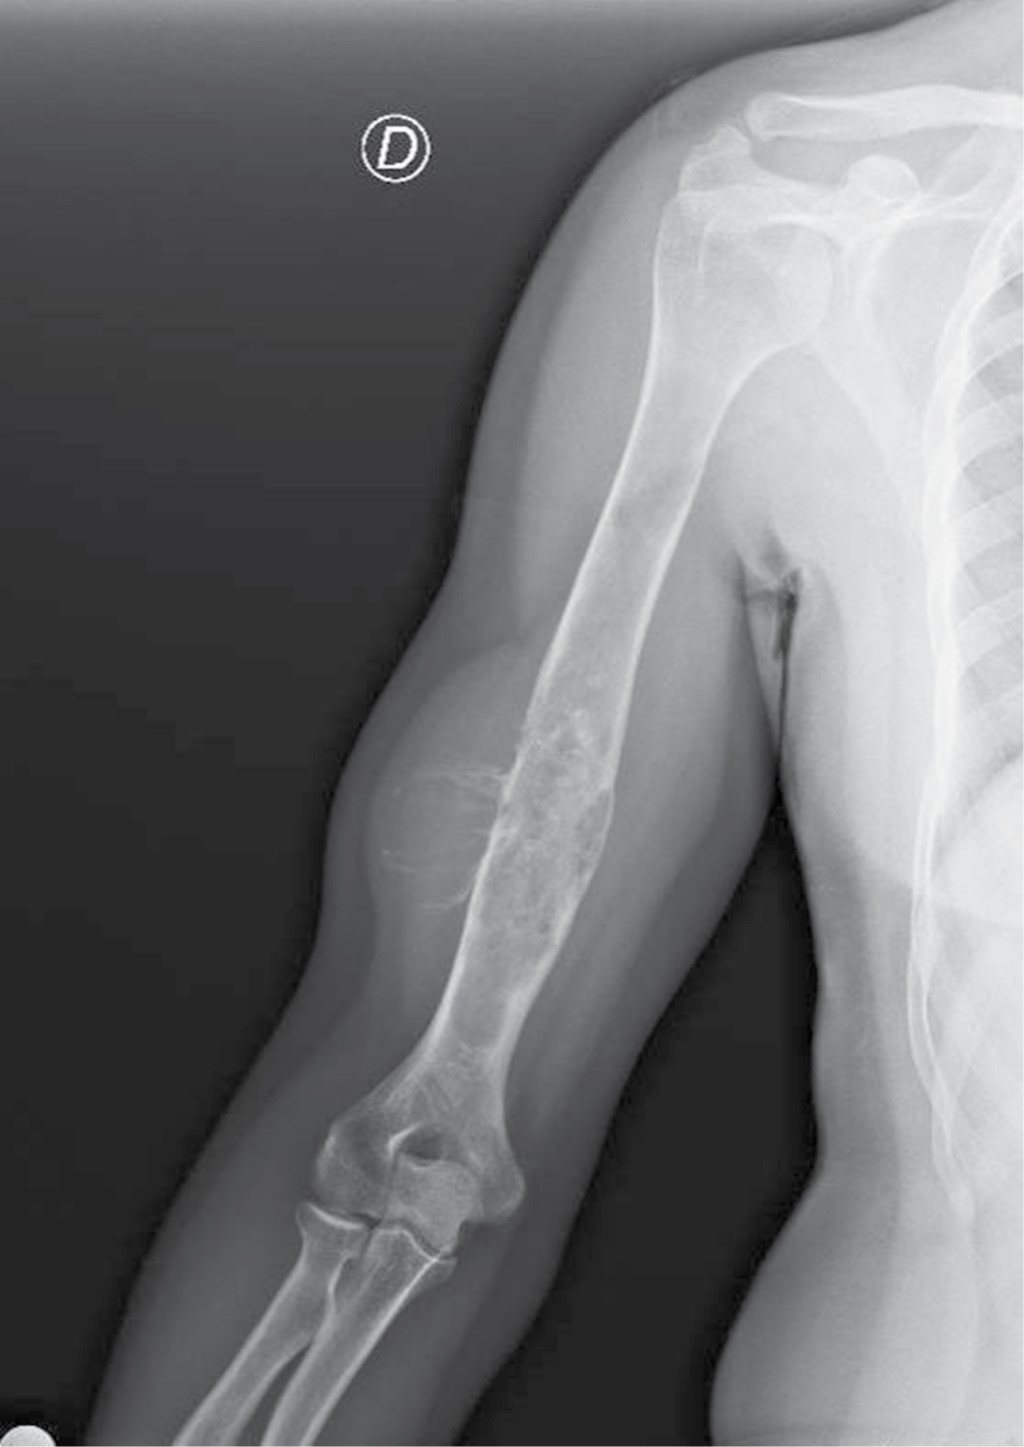

Contrast-enhanced MRI showed an infiltrative, diffuse endosteal lesion affecting the humeral shaft extending 19 cm longitudinally from the humeral neck to the supracondylar region, infiltrating and destroying the cortex in the lateral margin of the middle third of the diaphysis. The scan also revealed a soft tissue mass involving the deep muscle groups on the posterolateral aspect of the arm that measured approximately 7.8 × 4.9 × 2.6 cm in diameter (lateral1anteroposterior1transverse). The tumor signal was predominantly high on the T2 sequences, with hemorrhagic content and a focal juxtacortical tumor component toward the posterior and medial margins measuring 2.4 cm and presenting with marked diffusion restriction and contrast enhancement, suggesting a large tumor component in this segment. Peripheral enhancement of the tumor lesion was also observed, and there were no displaced or angled fractures. Tumor involvement was not observed in the proximal or distal epiphysis of the humerus. The humeral vascular bundle running along the medial aspect of the arm did not demonstrate signs of tumor infiltration, but branches supplying the tumor were observed emerging from the distal brachial artery.

The dimensions for surgical planning were confirmed on MRI following an assessment of bone extension and soft tissue involvement on the different planes (Figure 2).

Figure 2